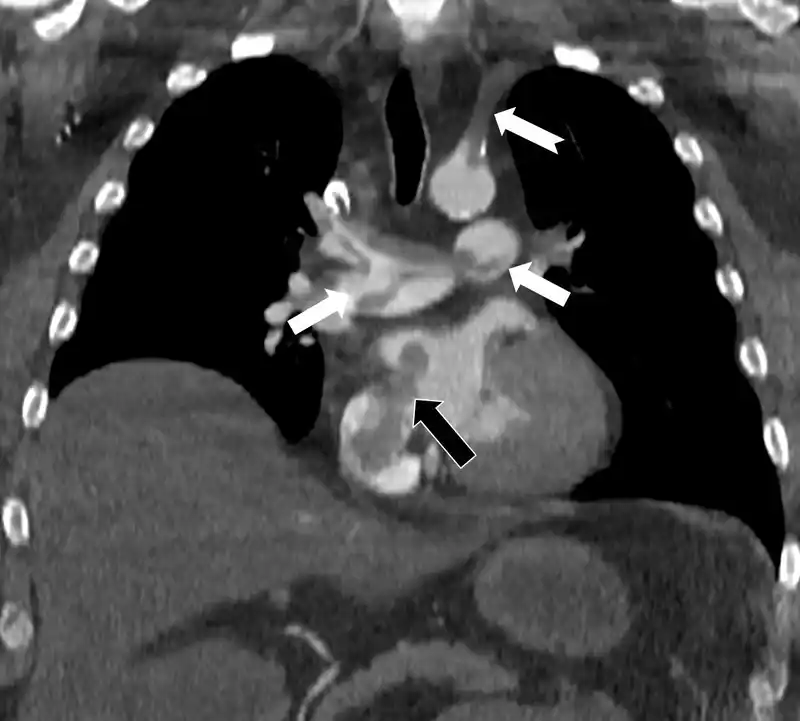

Yapılan ileri görüntüleme tetkikleri, hastadaki hayati tehlikenin kaynağını net bir şekilde gösterdi. Akciğerin bilgisayarlı tomografi anjiyografisi, toplar damarlardan kaynaklanan bir pıhtının akciğer damarlarını tıkamasının yanı sıra, daha önce fark edilmemiş bir kalp deliğinden (atrial septal defekt) geçerek kalbin sağ tarafından sol tarafına ulaştığını ve ana atardamara girerek sol kol damarını tıkadığını ortaya çıkardı. Bu durum, 'paradoks emboli' olarak adlandırılan ciddi bir tabloydu.